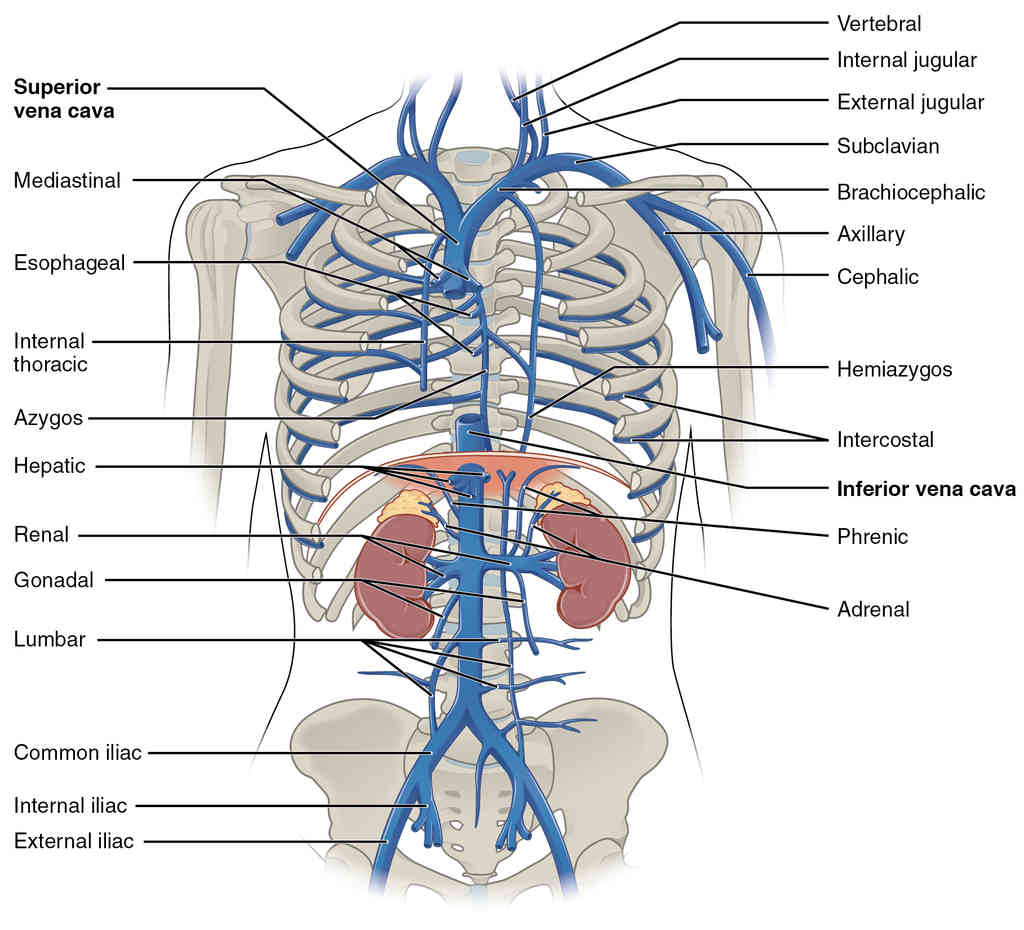

This page is under construction. For now, it is just a resource of the images found in the OpenStax Anatomy and Physiology Handbook. It wil slowly change into a revision tool. Each slide has a number. Use this to refer to the slide. When completed, it will have an unlabelled section, with labelled slides in parallel. On the unlabelled slides, write your answer and use the labelled slide to assess yourself. Keep track by also noting the number on each slide. Improvement at each attempt is important, more so than full marks on a first attempt.